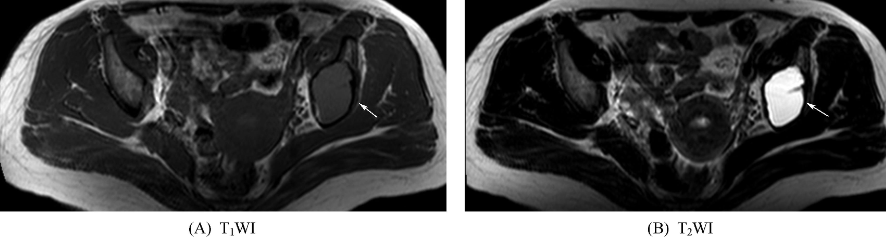

十、骨囊肿

好发于长管状骨干骺端的松质骨或骨干的髓腔内,多位于中心,一般为单囊,少数为多囊。表现为圆形或卵圆形的长T1、长T2信号影,周边可有一低信号的硬化环(图10),增强扫描无强化。邻近皮质可膨胀变薄,但其膨胀程度一般不超过干骺端宽度,病变长轴与骨干平行。一般无骨膜反应。骨囊肿可发生病理性骨折。

图10 骨囊肿左侧髂骨内见类圆形长T1、长T2信号影,边界清晰,见低信号硬化缘。